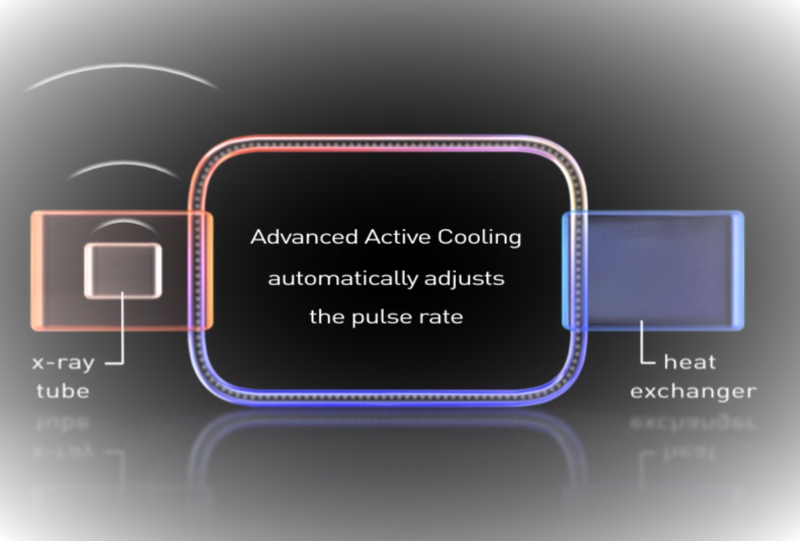

Унікальна

система замкнутого активного охолодження Advanced Active Cooling для забезпечення низької температури генератора та запобігання відмови системи через перегрів, завдяки чому досягається найбільша серед існуючих мобільних ангіографів теплоємність блоку рентгенівської трубки 10 000 000 теплових одиниць. Ця система гарантує безперервне використання мобільного ангіографу навіть під час найтриваліших операціях.

Цифрові плоскопанельні детектори з технологією CMOS розмірами 20,5х20,5 см або 31х31 см з більш високою роздільною здатністю завдяки меншому розміру пікселів у поєднанні з більш низьким рівнем шуму і більш високою швидкістю зчитування. Унікальна система замкнутого активного охолодження Advanced Active Cooling для забезпечення низької температури генератора та запобігання відмови системи через перегрів, завдяки чому досягається найбільша серед існуючих мобільних ангіографів теплоємність блоку рентгенівської трубки 10 000 000 теплових одиниць. Ця система гарантує безперервне використання мобільного ангіографу навіть під час найтриваліших операціях.

Унікальна система замкнутого активного охолодження Advanced Active Cooling для забезпечення низької температури генератора та запобігання відмови системи через перегрів, завдяки чому досягається найбільша серед існуючих мобільних ангіографів теплоємність блоку рентгенівської трубки 10 000 000 теплових одиниць. Ця система гарантує безперервне використання мобільного ангіографу навіть під час найтриваліших операціях. Повний пакет програмного забезпечення для кардіосудинної застосувань, у т. ч. цифрова субтракційна ангіографія (DSA), ангіографія з максимальним контрастуванням (MSA) і картируванням (RSA), Pixel Shift / Landmarking, частота 25 кадрів за секунду, використання як традиційних контрастних речовин, так і СО2.